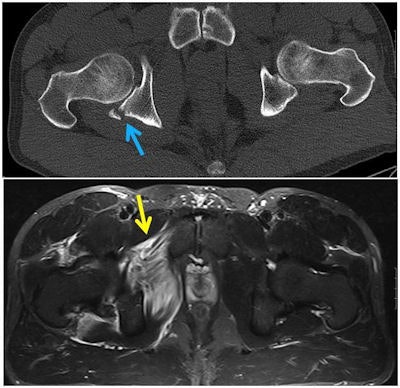

A 40-year-old male mountain biker presented with acute, right-sided hip pain after hitting an unexpected dip while riding a downhill single track in the dark. Axial CT image (top) shows a right posterior acetabular fracture (blue arrow). Axial T2-weighted fat-suppressed MRI (bottom) demonstrates a tear of the right adductor magnus (yellow arrow). All images courtesy of Drs. Daichi Hayashi, PhD, Richard de Villiers, and Shaun Scheepers.Mountain biking is a popular recreational and competitive sport worldwide, but bikers incur serious injuries due to high velocity falls in off-road situations, despite use of protective gear. In their research, Hayashi and his colleagues sought to illustrate the types and mechanisms of musculoskeletal injuries of the neck, torso, and extremities sustained by mountain bikers and to highlight the importance of multimodality imaging, including radiography, CT, MRI, and ultrasound, in clinical management.